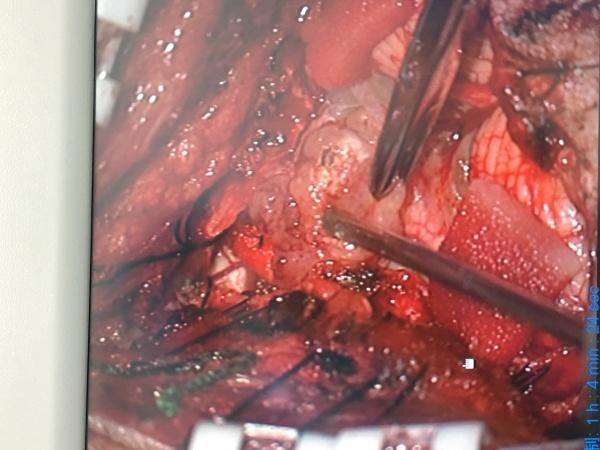

果然如我们术前预料,两侧的小脑后下动脉完整包绕在肿瘤组织之中,以超声刀和吸引器小心分离(见上图中两根迂曲的动脉),分离完整后才是最困难的,我们需要在两根迂曲血管的间隙中继续向下分离至脑干(延髓),万幸!肿瘤与延髓表面有明确的分界,所以考虑室管膜瘤可能大,而术中的冰冻也证明了我们的想法.